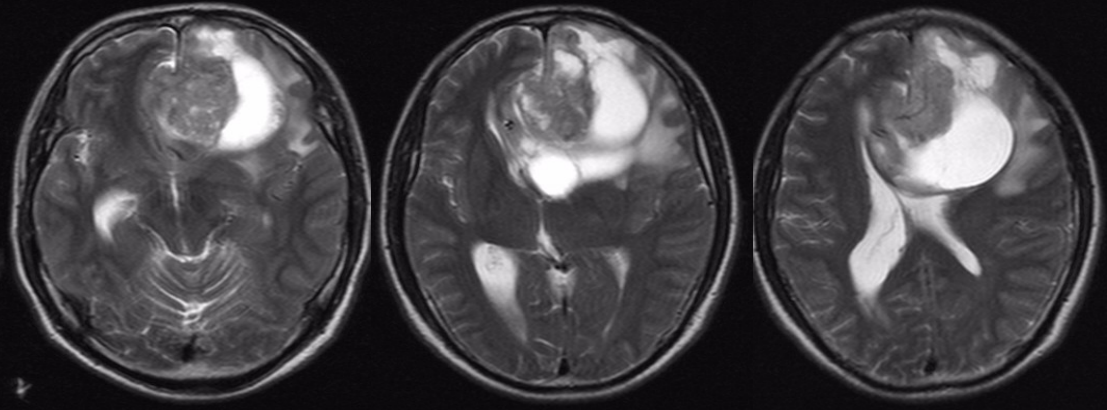

术后半年MRI增强